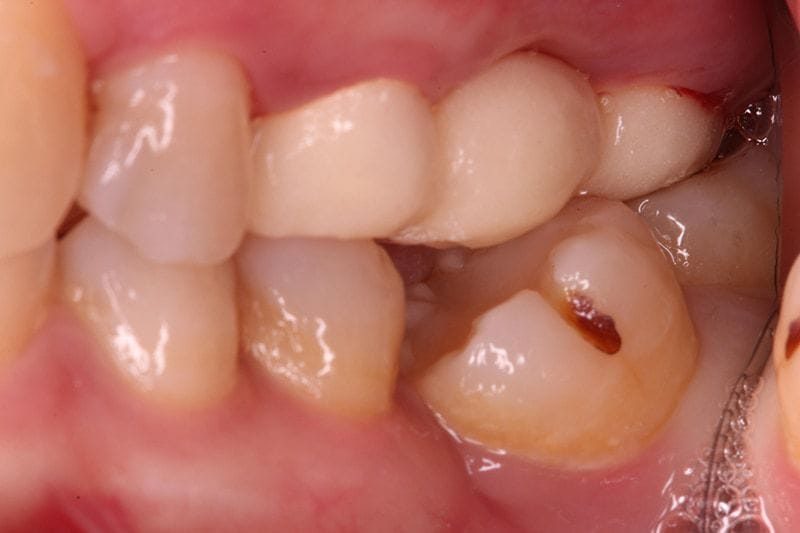

左下區域很早第一大臼齒就缺牙。因為缺牙不補,久了以後齒列空間改變,後面兩顆臼齒往前傾倒,造成吃東西時食物堆積難以清潔的問題。左邊上面後方假牙,時間久遠,密合度已經不佳,這會是清潔的死角,因而造成牙菌斑堆積導致牙齦發炎流血。

圖示:傾倒的鄰牙產生清潔死角,造成牙齦發炎流血 圖示:智齒拔除後放置骨釘矯正第二大臼齒,恢復第一大臼齒空間